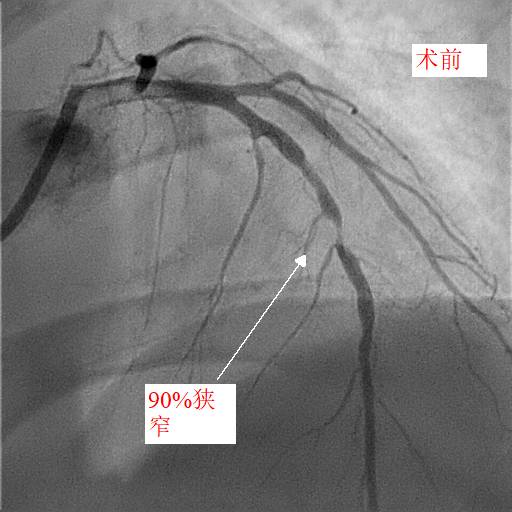

第二天,小天和父亲同一天接受冠脉造影和手术治疗,冠脉造影进一步明确了:小天冠状动脉回旋支完全堵死、前降支90%堵塞,而右冠状动脉也仅有一丝血流通过。造影中医生发现,小天的血管狭窄已经有一段时间,其中的右冠状动脉已经产生了侧支循环。随后医生在患者右冠状动脉里放入了两个支架,恢复了血流。

康慧元医生说:“患者的三条心脏血管都严重堵塞,很容易发生急性心梗甚至猝死,手术先开通慢性堵塞的右冠状动脉,保证心脏有足够的血流。”